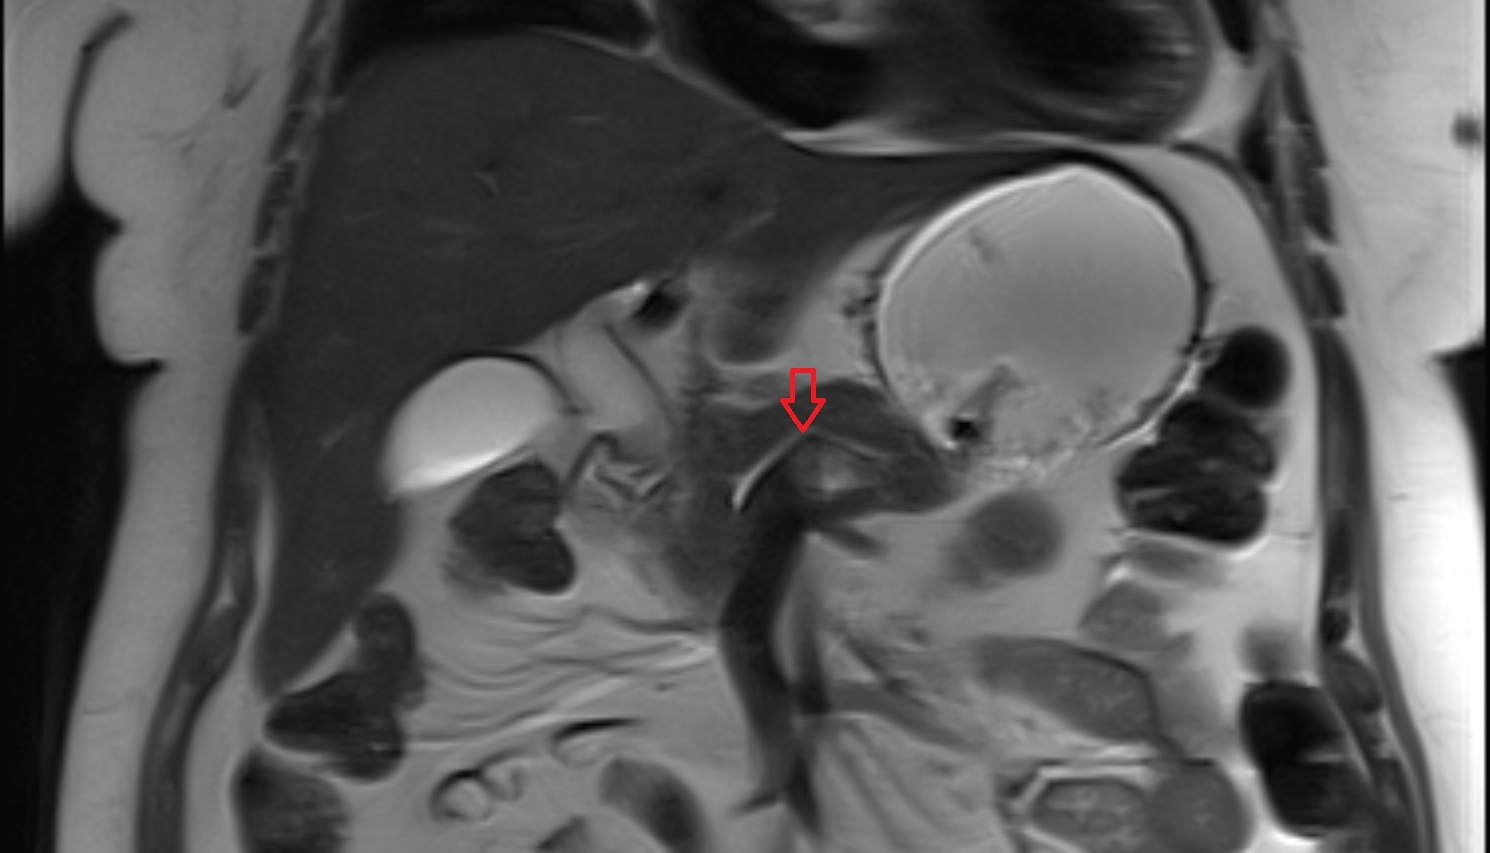

- Placenta

- Uterus (pregnancy)

- Amniotic fluid

- Umbilical cord

- Urinary Bladder in Pregnancy

- Cervix in Pregnancy

- Vagina in Pregnancy

- Fundus of uterus in pregnancy

- Fetal brain

- Fetal caudate nucleus

- Fetal thalamus

- Fetal pons

- Fetal cerebellum

- Fetal occipital lobe

- Fetal temporal lobe

- Fetal parietal lobe

- Fetal frontal lobe

- Fetal third ventricle

- Fetal fourth ventricle

- Fetal lateral ventricle

- Fetal superior sagittal sinus

- Fetal straight sinus

- Fetal transverse sinus

- Fetal sigmoid sinus

- Fetal cervical spine

- Fetal thoracic spine

- Fetal lumbar spine

- Fetal spinal cord

- Fetal Eyes

- Fetal paranasal sinuses

- Fetal tooth buds

- Maternal ovaries

- Fetal shoulder

- Fetal lungs

- Fetal Ribs

- Fetal trachea

- Fetal Heart

- Fetal aorta

- Fetal upper arm

- Fetal knee

- Fetal ankle

- Fetal foot

- Fetal thigh

- Fetal Lower Leg

- Fetal forearm

- Fetal Liver

- Fetal small bowel

- Fetal hand

- Fetal urinary bladder

- Fetal kidneys

- Fetal rectum

- Fetal elbow

- Fetal wrist

- Fetal hip

- Fetal anus

- Fetal Fingers

- Fetal buttock

- Fetal scrotum

- Fetal testis

- Fetal penis

- Fetal colon

- Fetal stomach

- Fetal spinal canal